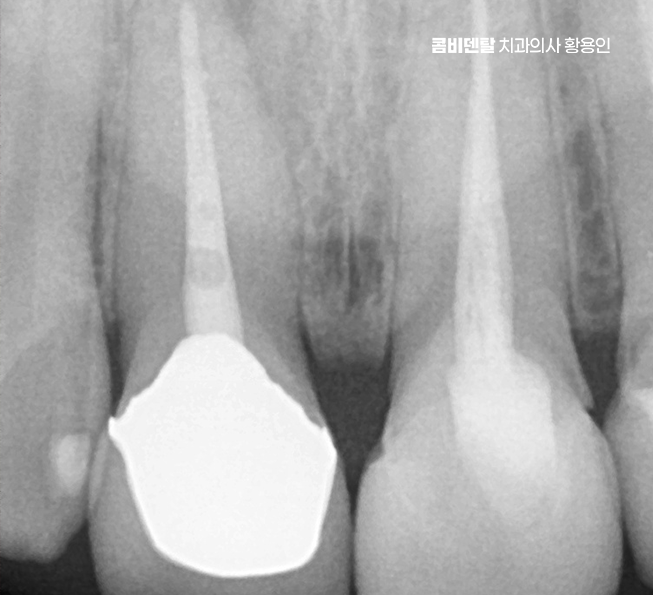

이런 경우 처음엔 잇몸이 붓거나 피가 나는 가벼운 증상으로 시작될 수 있지만 그 아래에서는 이미 보철물 안쪽 치아가 썩고 있거나, 보철물 아래 충치가 진행됐을 수 있으며 특히 오래된 보철물은 접착제가 이미 닳아 있거나 밀착력이 떨어져 있어서 세균이 쉽게 침투할 수 있어서 이런 식의 2차 충치는 눈으로 보이지 않기 때문에, 문제가 꽤 심각해졌을 때야 느끼게 되는 경우가 많은 거예요

문제가 심해지면 결국 신경에까지 세균이 도달해서 통증이 생기고 찬물에 시리거나, 저리듯이 쑤시는 느낌, 잇몸에 작은 뾰루지가 생기는 경우도 있으며 그냥 손가락으로 눌렀을 때 묵직한 압통이 있다면 이미 신경치료가 필요한 상태일 가능성이 높아지고 이런 경우엔 기존 보철물을 제거하고, 내부 충치 상태를 확인한 뒤, 신경치료부터 들어가야 할 수 있었어요

신경치료는 치아 내부의 염증이나 감염된 신경을 제거하고, 뿌리 속을 소독해서 밀봉하는 치료로 앞니는 뿌리가 하나인 경우가 대부분이라 어금니보단 비교적 간단하지만, 이미 보철을 한 치아는 구조적으로 약해져 있기 때문에 세심한 처치가 필요한데 뿌리 일부가 약해져 있거나 균열이 생겨 있을 가능성도 있어서 이런 경우엔 정밀한 신경치료가 필요하며 감염이 심한 경우엔 2~3회에 걸쳐 치료가 이뤄지고, 상태가 안정된 뒤에 마무리되는 거예요.